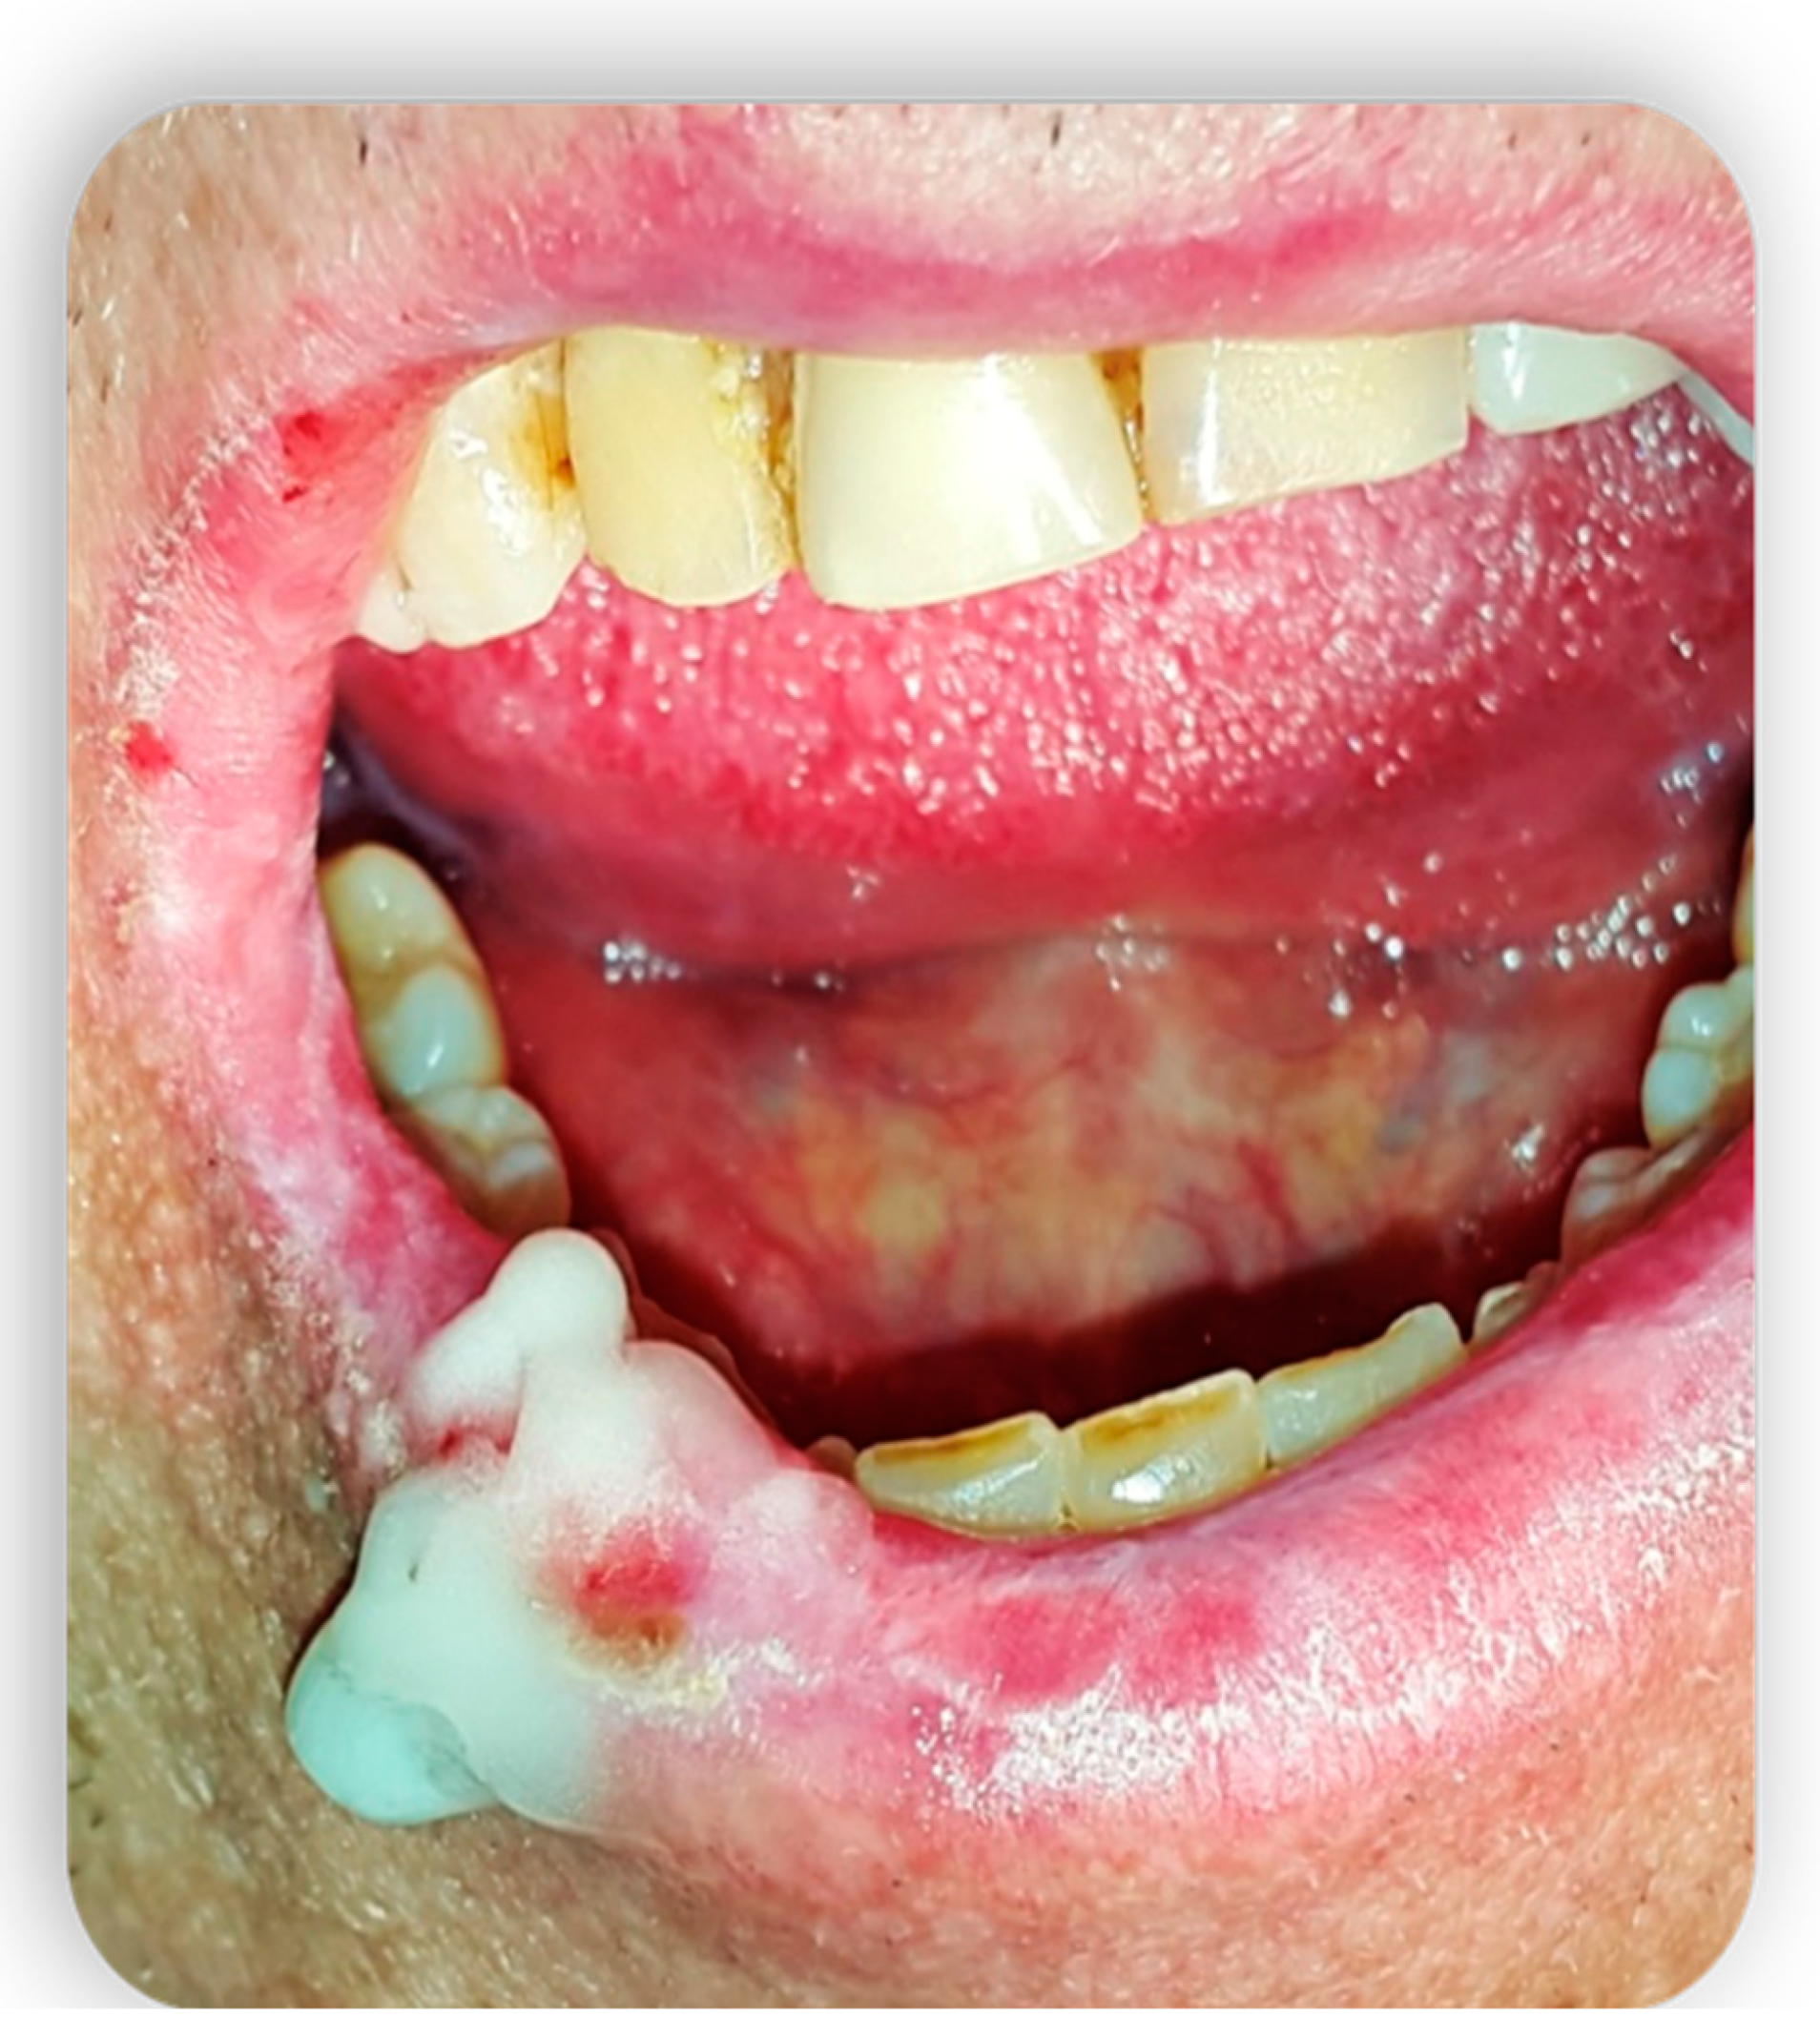

3. Topical Treatment of Oral Lesions

The systemic treatment of the disease consists of immunosuppressive drugs but only in a few cases leads to the healing of oral lesions [38]. These patients could benefit from topical agents, both to focus the action exclusively on the regions of interest and to reduce the state of systemic immunosuppression. In these cases, it is very common to use steroid preparations for topical use such as the combination of fluocinonide and clobetasol, or dexamethasone and betamethasone [40]. The topical application of CSA has also been used successfully in lichenoid manifestations of the mucous membranes and in cases of punctate keratitis. In addition, the application of topical preparations of azathioprine, in association with systemic immunosuppressive therapy, was evaluated in patients with skin ulcerative lesions that are resistant to topical treatment with CSA and cortisone [41]. The results, although obtained from a small number of patients, showed a good response to treatment considering both the extension of the ulcerated areas and pain. Several reports also indicate tacrolimus, already known in the dermatological field for its beneficial effects in atopic dermatitis, as a possible topical agent in the treatment of cutaneous cGVHD [42] (Figure 7 and Figure 8).

Figure 7.

Topical treatment with non-transfusional hemocomponents.

Figure 8.